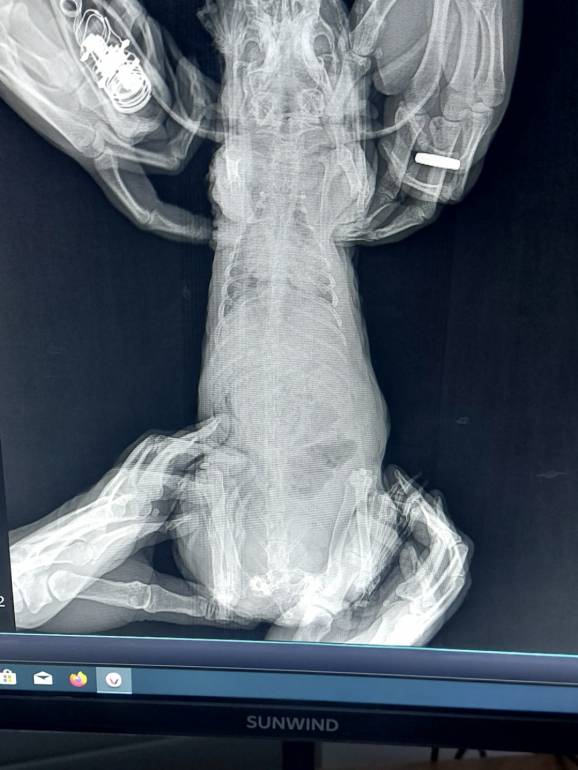

Здравствуйте Алексей. Взяла с рук зайца декоративного. При осмотре у врача были поставлены следующие диагнозы:саркома с метастазами в области сердца. опухоль достаточно плотная. Один глаз видит,втооой нет (на обоих глазах белая пелина),присутствует небольшой коньюктивит. Сильная анемия. Анализы не сдавали,врач не советовала,осмотрела только мордочку. Операцию не советует,тк метастазы. Больше месяца назпд,когда я его увидела вся спина и мордочка были лысыми,скорее всего из-за того,что ему редко меняли наполнитель,воды не давали,сено не ел. Я посоветовала использовать мазь санодерн (состав гепар сульфур,хамомилла рекутита,беладонна,кплендула). Через месяц зайчик полностью оброс. Я его дома уже помыла,когда забрала

Возраст 9 лет,слизистые влажные,аппетит очень хороший,не кусается,спокойный.

Врач выписала лечение: метастоп 1 таб ежедневно и железо феррум лен по 0,05 мл 1 р. в нед.

Подскажите пожалуйста,что можно сделать в данной ситуации.Если подскажите лечение,давать препараты,которые выписал врач? Врач,который делал ренген,сказал,сто если делать уколы железа,то это наоборот очень опасно. Спасибо огромное за консультацию